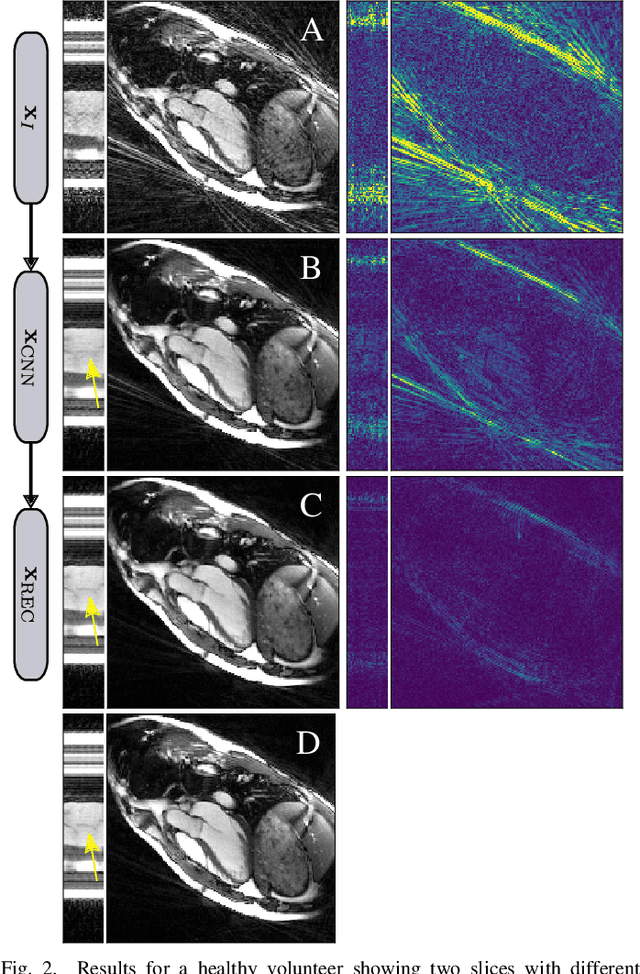

Abstract:Purpose: Iterative Convolutional Neural Networks (CNNs) which resemble unrolled learned iterative schemes have shown to consistently deliver state-of-the-art results for image reconstruction problems across different imaging modalities. However, because these methodes include the forward model in the architecture, their applicability is often restricted to either relatively small reconstruction problems or to problems with operators which are computationally cheap to compute. As a consequence, they have so far not been applied to dynamic non-Cartesian multi-coil reconstruction problems. Methods: In this work, we propose a CNN-architecture for image reconstruction of accelerated 2D radial cine MRI with multiple receiver coils. The network is based on a computationally light CNN-component and a subsequent conjugate gradient (CG) method which can be jointly trained end-to-end using an efficient training strategy. We investigate the proposed training-strategy and compare our method to other well-known reconstruction techniques with learned and non-learned regularization methods. Results: Our proposed method outperforms all other methods based on non-learned regularization. Further, it performs similar or better than a CNN-based method employing a 3D U-Net and a method using adaptive dictionary learning. In addition, we empirically demonstrate that even by training the network with only iteration, it is possible to increase the length of the network at test time and further improve the results. Conclusions: End-to-end training allows to highly reduce the number of trainable parameters of and stabilize the reconstruction network. Further, because it is possible to change the length of the network at test time, the need to find a compromise between the complexity of the CNN-block and the number of iterations in each CG-block becomes irrelevant.